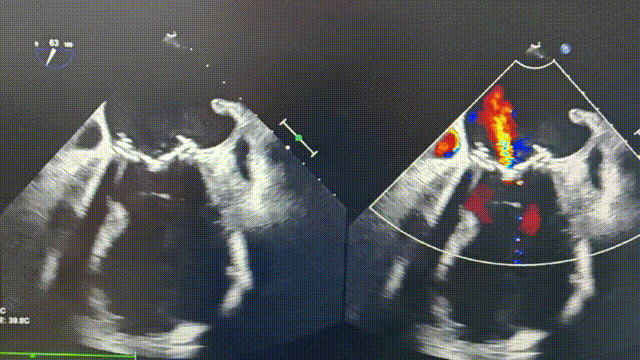

二尖瓣生物瓣退行性病变狭窄(重度)并反流(轻-中度)

术中影像

瓣膜初次释放位置偏深,第二次释放后位置理想、形态良好,无需球囊后扩

二尖瓣打开通畅,无瓣周漏;超声检查肺静脉无损伤。